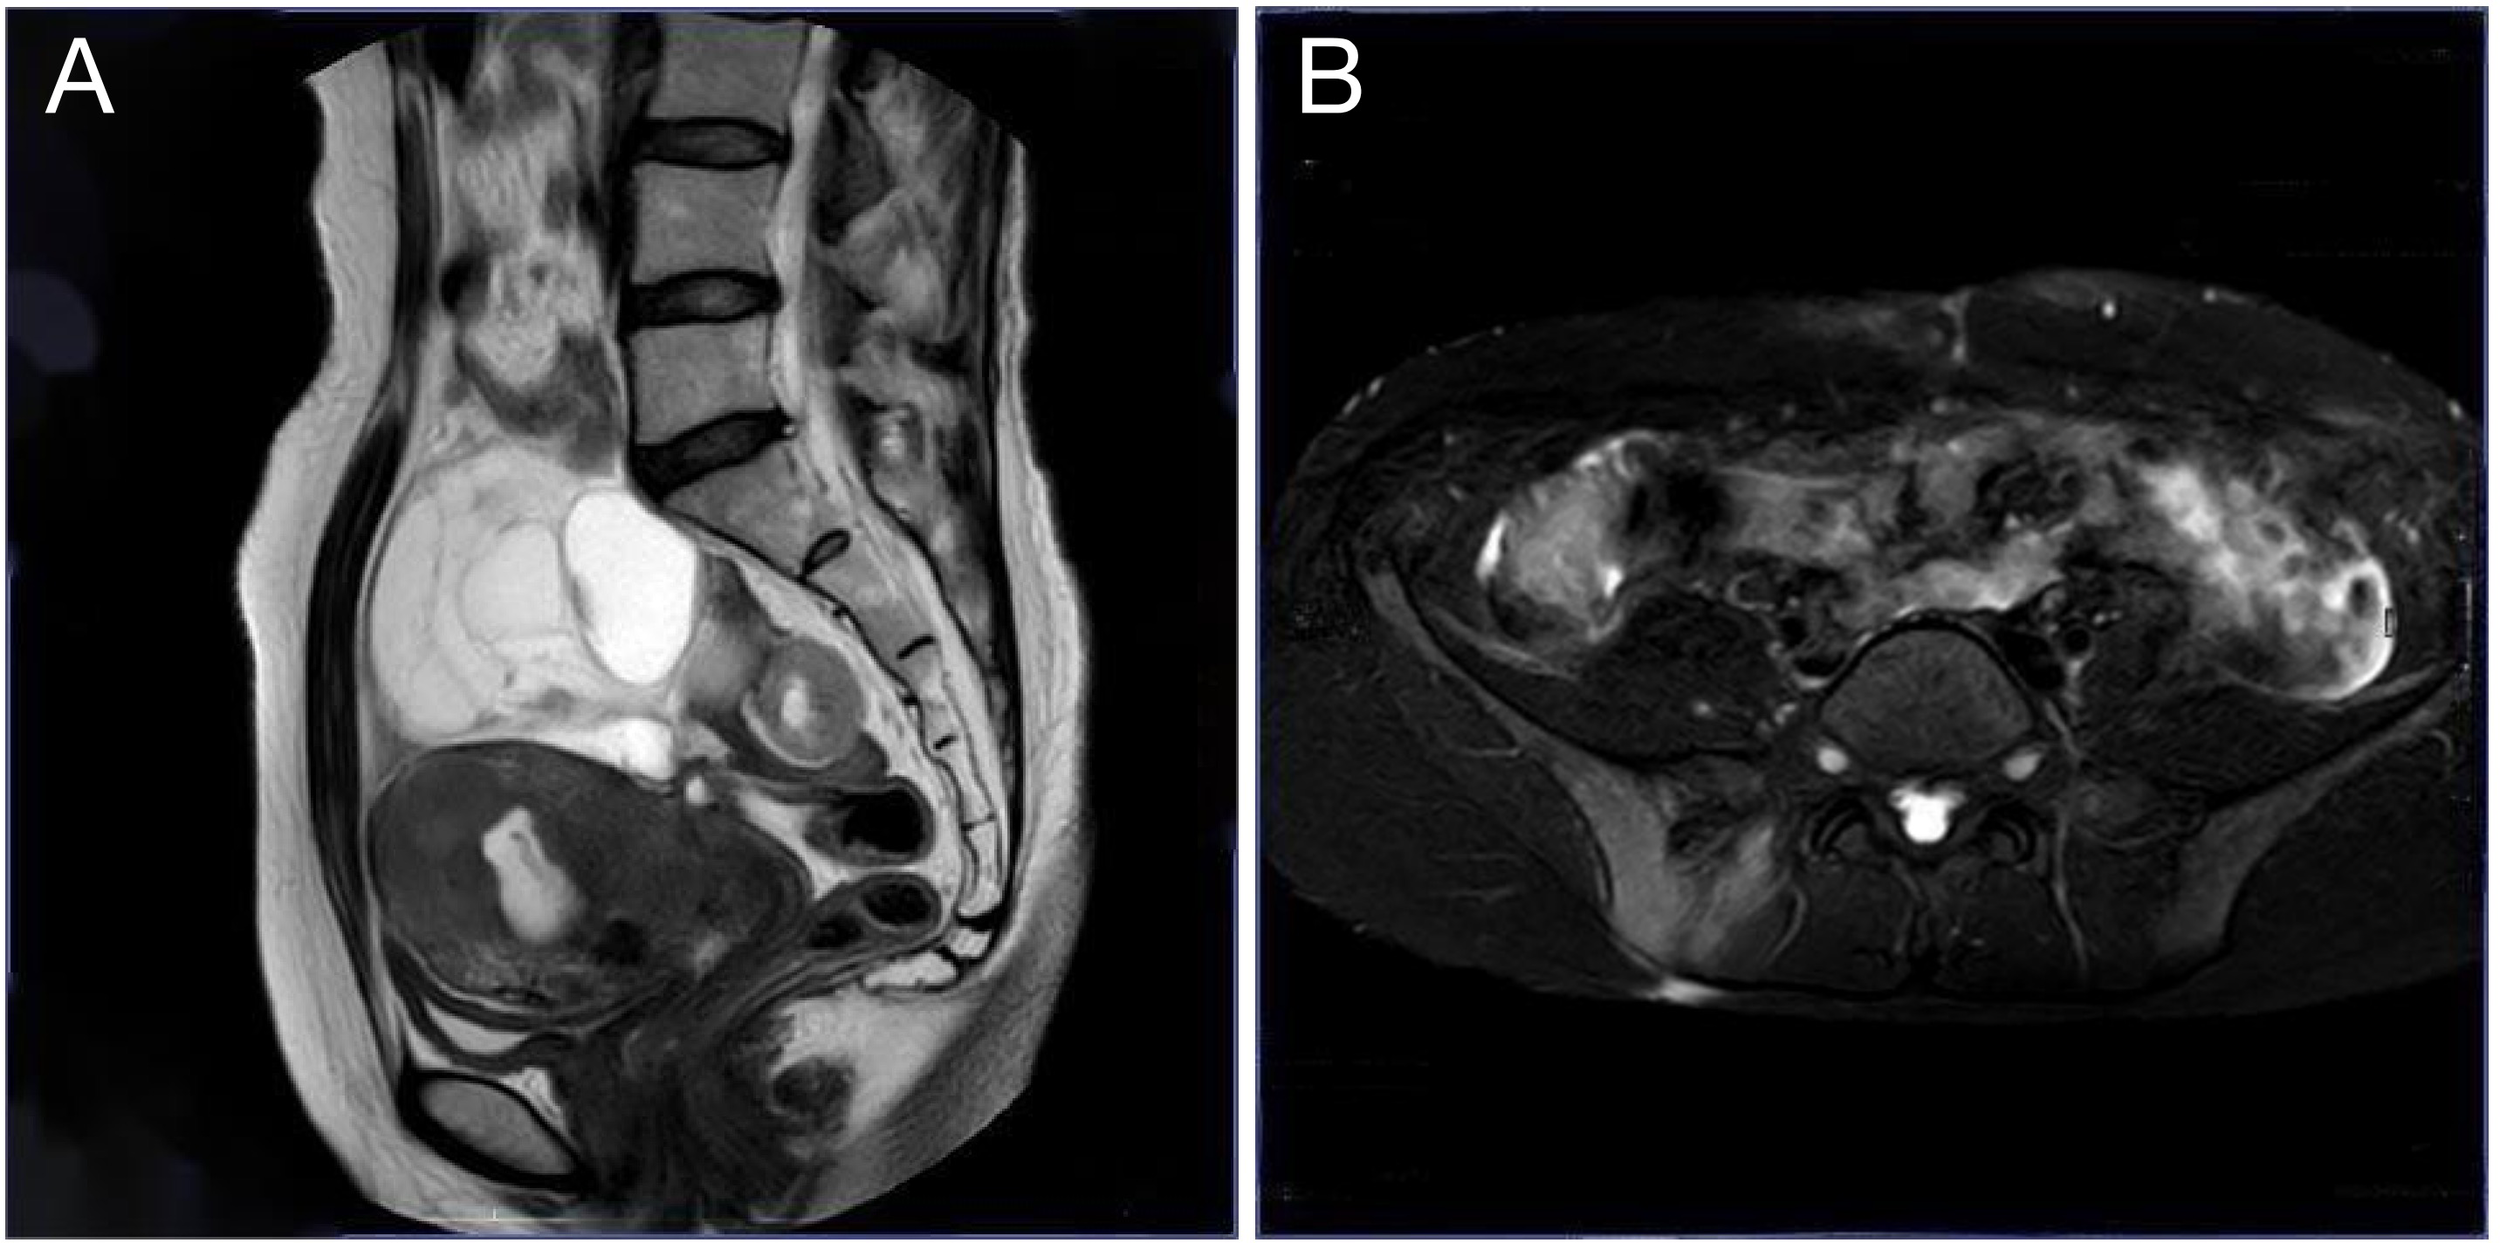

Upon readmission, pelvic examination revealed a markedly shortened, enlarged, irregularly shaped, and firm posterior cervical lip with restricted mobility and positive cervical motion tenderness. The uterus was enlarged to approximately 10-week size, firm, tender, and fixed. Bilateral adnexal masses were palpable (6 cm on the left, 10 cm on the right) with associated tenderness but no rebound or guarding. Laboratory testing revealed an anti-Müllerian hormone (AMH) level of 0.528 ng/mL, CA125 increased to 171.57 U/mL, human epididymis protein 4 (HE4) markedly elevated to 237.80 pmol/L, and carcinoembryonic antigen (CEA) mildly elevated at 5.14 ng/mL. Other tumor markers, including squamous cell carcinoma antigen (SCC), alpha-fetoprotein (AFP), carbohydrate antigen 15-3 (CA15-3), and carbohydrate antigen 19-9 (CA19-9), remained within normal ranges. Repeat TCT again indicated ASC-US. Imaging studies revealed a heterogeneous cervical echo pattern on transvaginal ultrasound, with an intrauterine separation measuring approximately 8 mm containing flocculent material. Two large adnexal masses with indistinct margins and internal vascularity were noted on either side of the uterus. In addition, hyperechoic hepatic lesions suggestive of hemangiomas were observed, along with polypoid changes in the gallbladder. Pelvic MRI demonstrated multiple ill-defined pelvic masses, abnormal signal changes in the right iliac crest and femoral head suggestive of malignancy, signal abnormalities in the uterus and cervix with hematometra, bilateral hydrosalpinges, as well as pelvic lymphadenopathy and effusion (Figure 2).

Figure 2

Pelvic MRI. (A) Sagittal T2-weighted image shows a cystic pelvic mass compressing the uterus and rectum; (B) Axial spectral attenuated inversion recovery (SPAIR) image highlights the mass with well-defined borders and involvement of the sacroiliac joints.